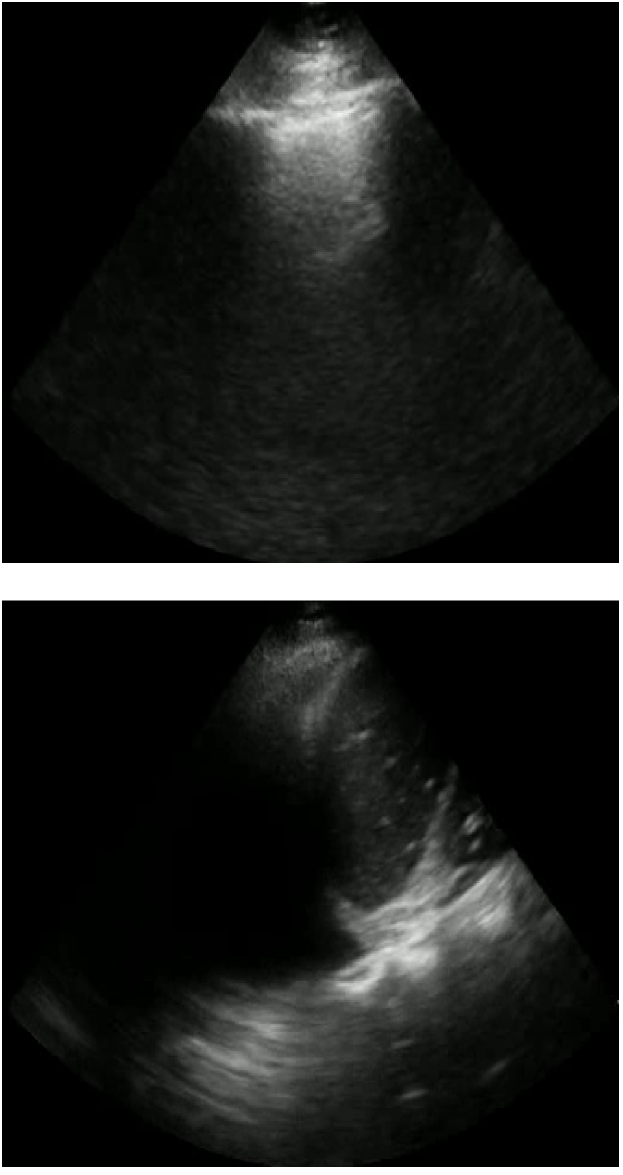

The LUS interpretative workflow addressed in this work has been described as a decision tree [19]. After determining the view, the interpreter traverses down the tree to look for increasingly specific artefacts that reduce a possible differential diagnosis. We focus on three binary classification tasks for LUS image interpretation: view classification (View), A-line versus B-line classification (A/B), and pleural effusion detection (PE). The former is applicable to parenchymal LUS views, and the latter to pleural LUS views. Table 1 summarizes these tasks, and Figure 1 displays emblematic examples for each class.

Refer to caption

(a) View: Parenchymal (top), pleural (bottom)

(b) AB: A-lines (top), B-lines (bottom)

(c) PE: No PE (top), PE (bottom)

Figure 2: Examples of each class for each LUS binary classification task: View (a), AB (b), and PE (c).